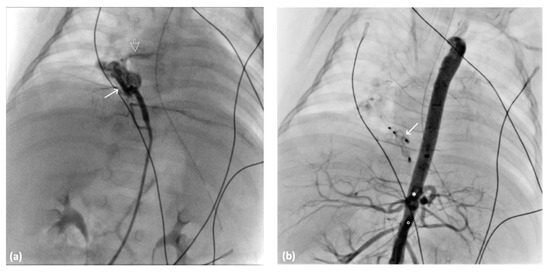

A 5-month-old full-term neonate experienced respiratory distress shortly after birth, with APGAR scores of 5 and 6 at 1 min and 5 min, respectively. Despite postintubation mechanical ventilatory support, the respiratory distress persisted. Cardiac sonography and chest CTA revealed an atrial septal defect and anomalous systemic arterial supply to the right lower lobe (Figure 5). The right lower lobe, posterior right upper lobe, and basal left lower lobe were affected by pneumonia. Cardiac catheterization was performed through the transfemoral approach by using a 4-Fr femoral sheath and catheter. Angiography revealed two engorged anomalous arteries originating from the abdominal aorta, forming a vessel sponge with rapid drainage into the pulmonary vein leading into the left atrium (Figure 6a). The anomalous arteries were embolized using 6 mm and 4 mm Amplatzer Vascular Plug II (AVP II; AGA Medical, Golden Valley, MN, USA) and a 4-Fr Judkins left catheter (Radifocus Optitorque, Terumo, Tokyo, Japan). After the deployment of the AVP, no residual shunt was observed (Figure 6b). Postembolization syndrome developed and subsided spontaneously. Although the respiratory condition initially improved after embolization, it later deteriorated due to respiratory failure arising from an uncontrollable lung infection. The patient succumbed to infection 2 months after embolization.

Figure 5.

Volume-rendering 3D reconstructive image displaying the anterior aberrant systemic artery (arrow) from the descending abdominal aorta (arrowhead), forming a vessel sponge in the right basal lung (curve arrow).

Figure 6.

Angiography images of 4-Fr Judking left catheter: (a) anomalous artery (arrow) creating a vessel sponge with pulmonary vein rapid drainage void (arrow) into the left atrium and (b) angiography image of the abdominal aorta after AVP II deployment (arrow) indicating no residual blood flow to the right lower lung. The ciliary trunk (*) and SMA (○) are presented.